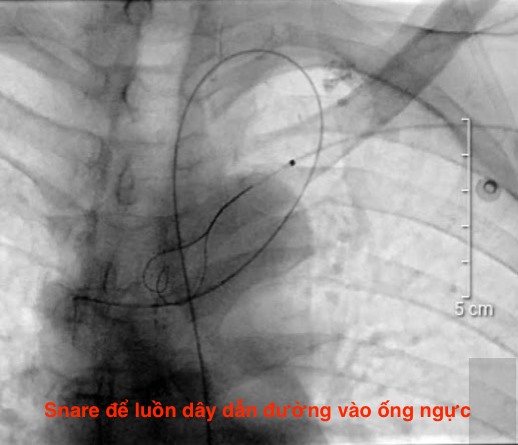

HỖ TRỢ BỆNH NHÂN TIM MẠCH

PGS.TS.BS.Hoàng Anh Tiến

Phó Giám đốc Trung tâm Tim mạch, Phó Trưởng Khoa Nội Tim mạch

BỆNH VIỆN TRƯỜNG ĐẠI HỌC Y DƯỢC HUẾ

HỖ TRỢ BỆNH NHÂN TIM MẠCH

PGS.TS.BS.Hoàng Anh Tiến

Phó Giám đốc Trung tâm Tim mạch, Phó Trưởng Khoa Nội Tim mạch

BỆNH VIỆN TRƯỜNG ĐẠI HỌC Y DƯỢC HUẾ